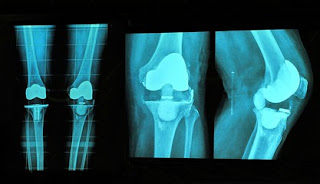

- Complete history and physical examination of the candidate

- X-ray examination to assess the total amount of damage caused

- Blood tests are also done to prevent inflammatory arthritis.